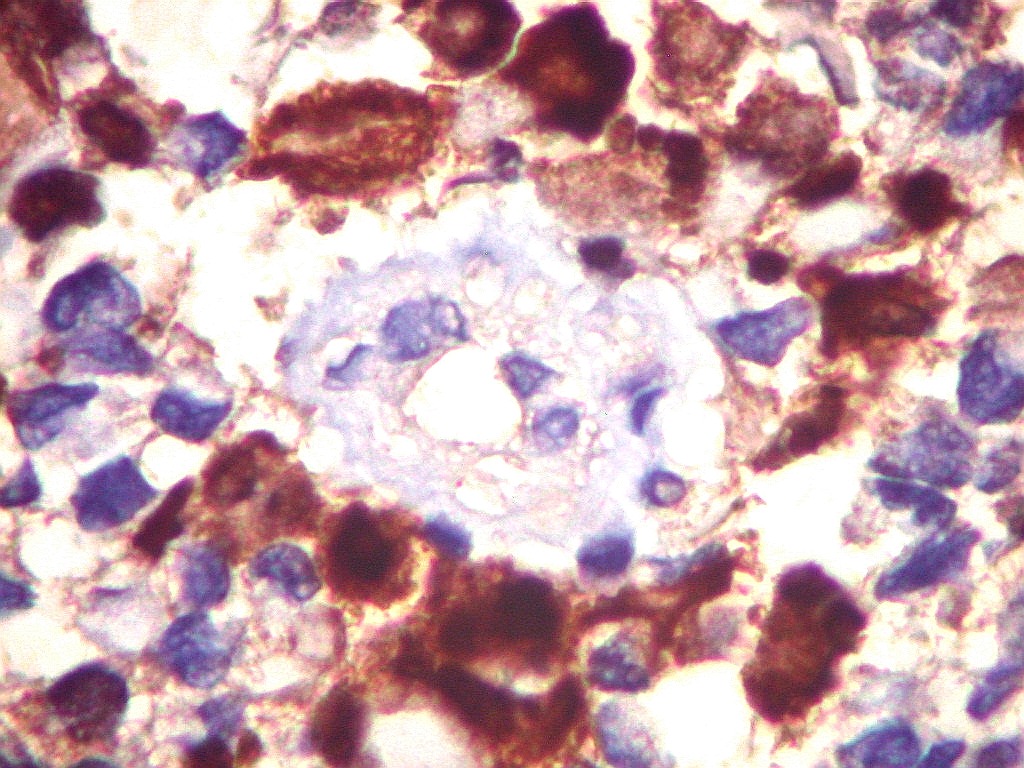

S-100.   Proteína S100 é expressa em células originadas da crista neural, como melanócitos e células de Schwann, e em macrófagos.  Aqui é observada em parte das células tumorais, em positividade nuclear e citoplasmática.